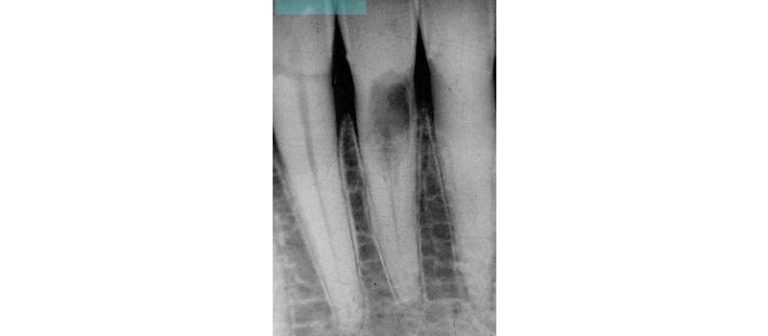

Vertical Root Fractures: The Diagnostic Dilemma and Hidden Menace

Discover why early recognition of root fractures is necessary for the success of endodontic treatment.By Lou Berman